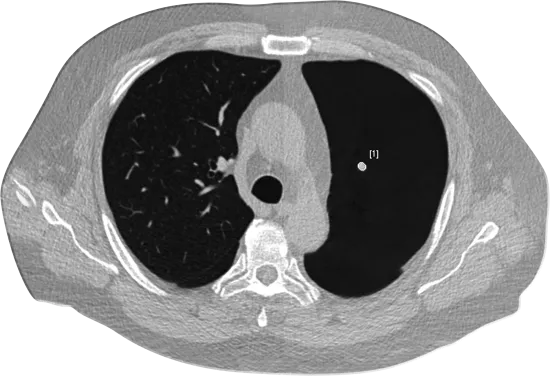

Lung cancer, cardiac disease and emphysema are leading global killers. Earlier detection and treatments of these conditions improves patient outcomes. However, detection is complex and time-consuming. The ClearRead TM cardiothoracic AI suite is purpose-built to improve accuracy and efficiency on chest CTs and X-rays, covering all the bases for a population health approach to the early detection of cardiothoracic conditions.

Our ClearRead Chest imaging interpretation solutions are built upon advanced AI algorithms that target the biggest health threats globally. We accurately and efficiently improve outcomes for improved patient care with tools that target pulmonary nodules, coronary artery calcification (CAC), and pneumothoraces. Learn more about the ClearRead solutions built for lung and cardiac conditions.